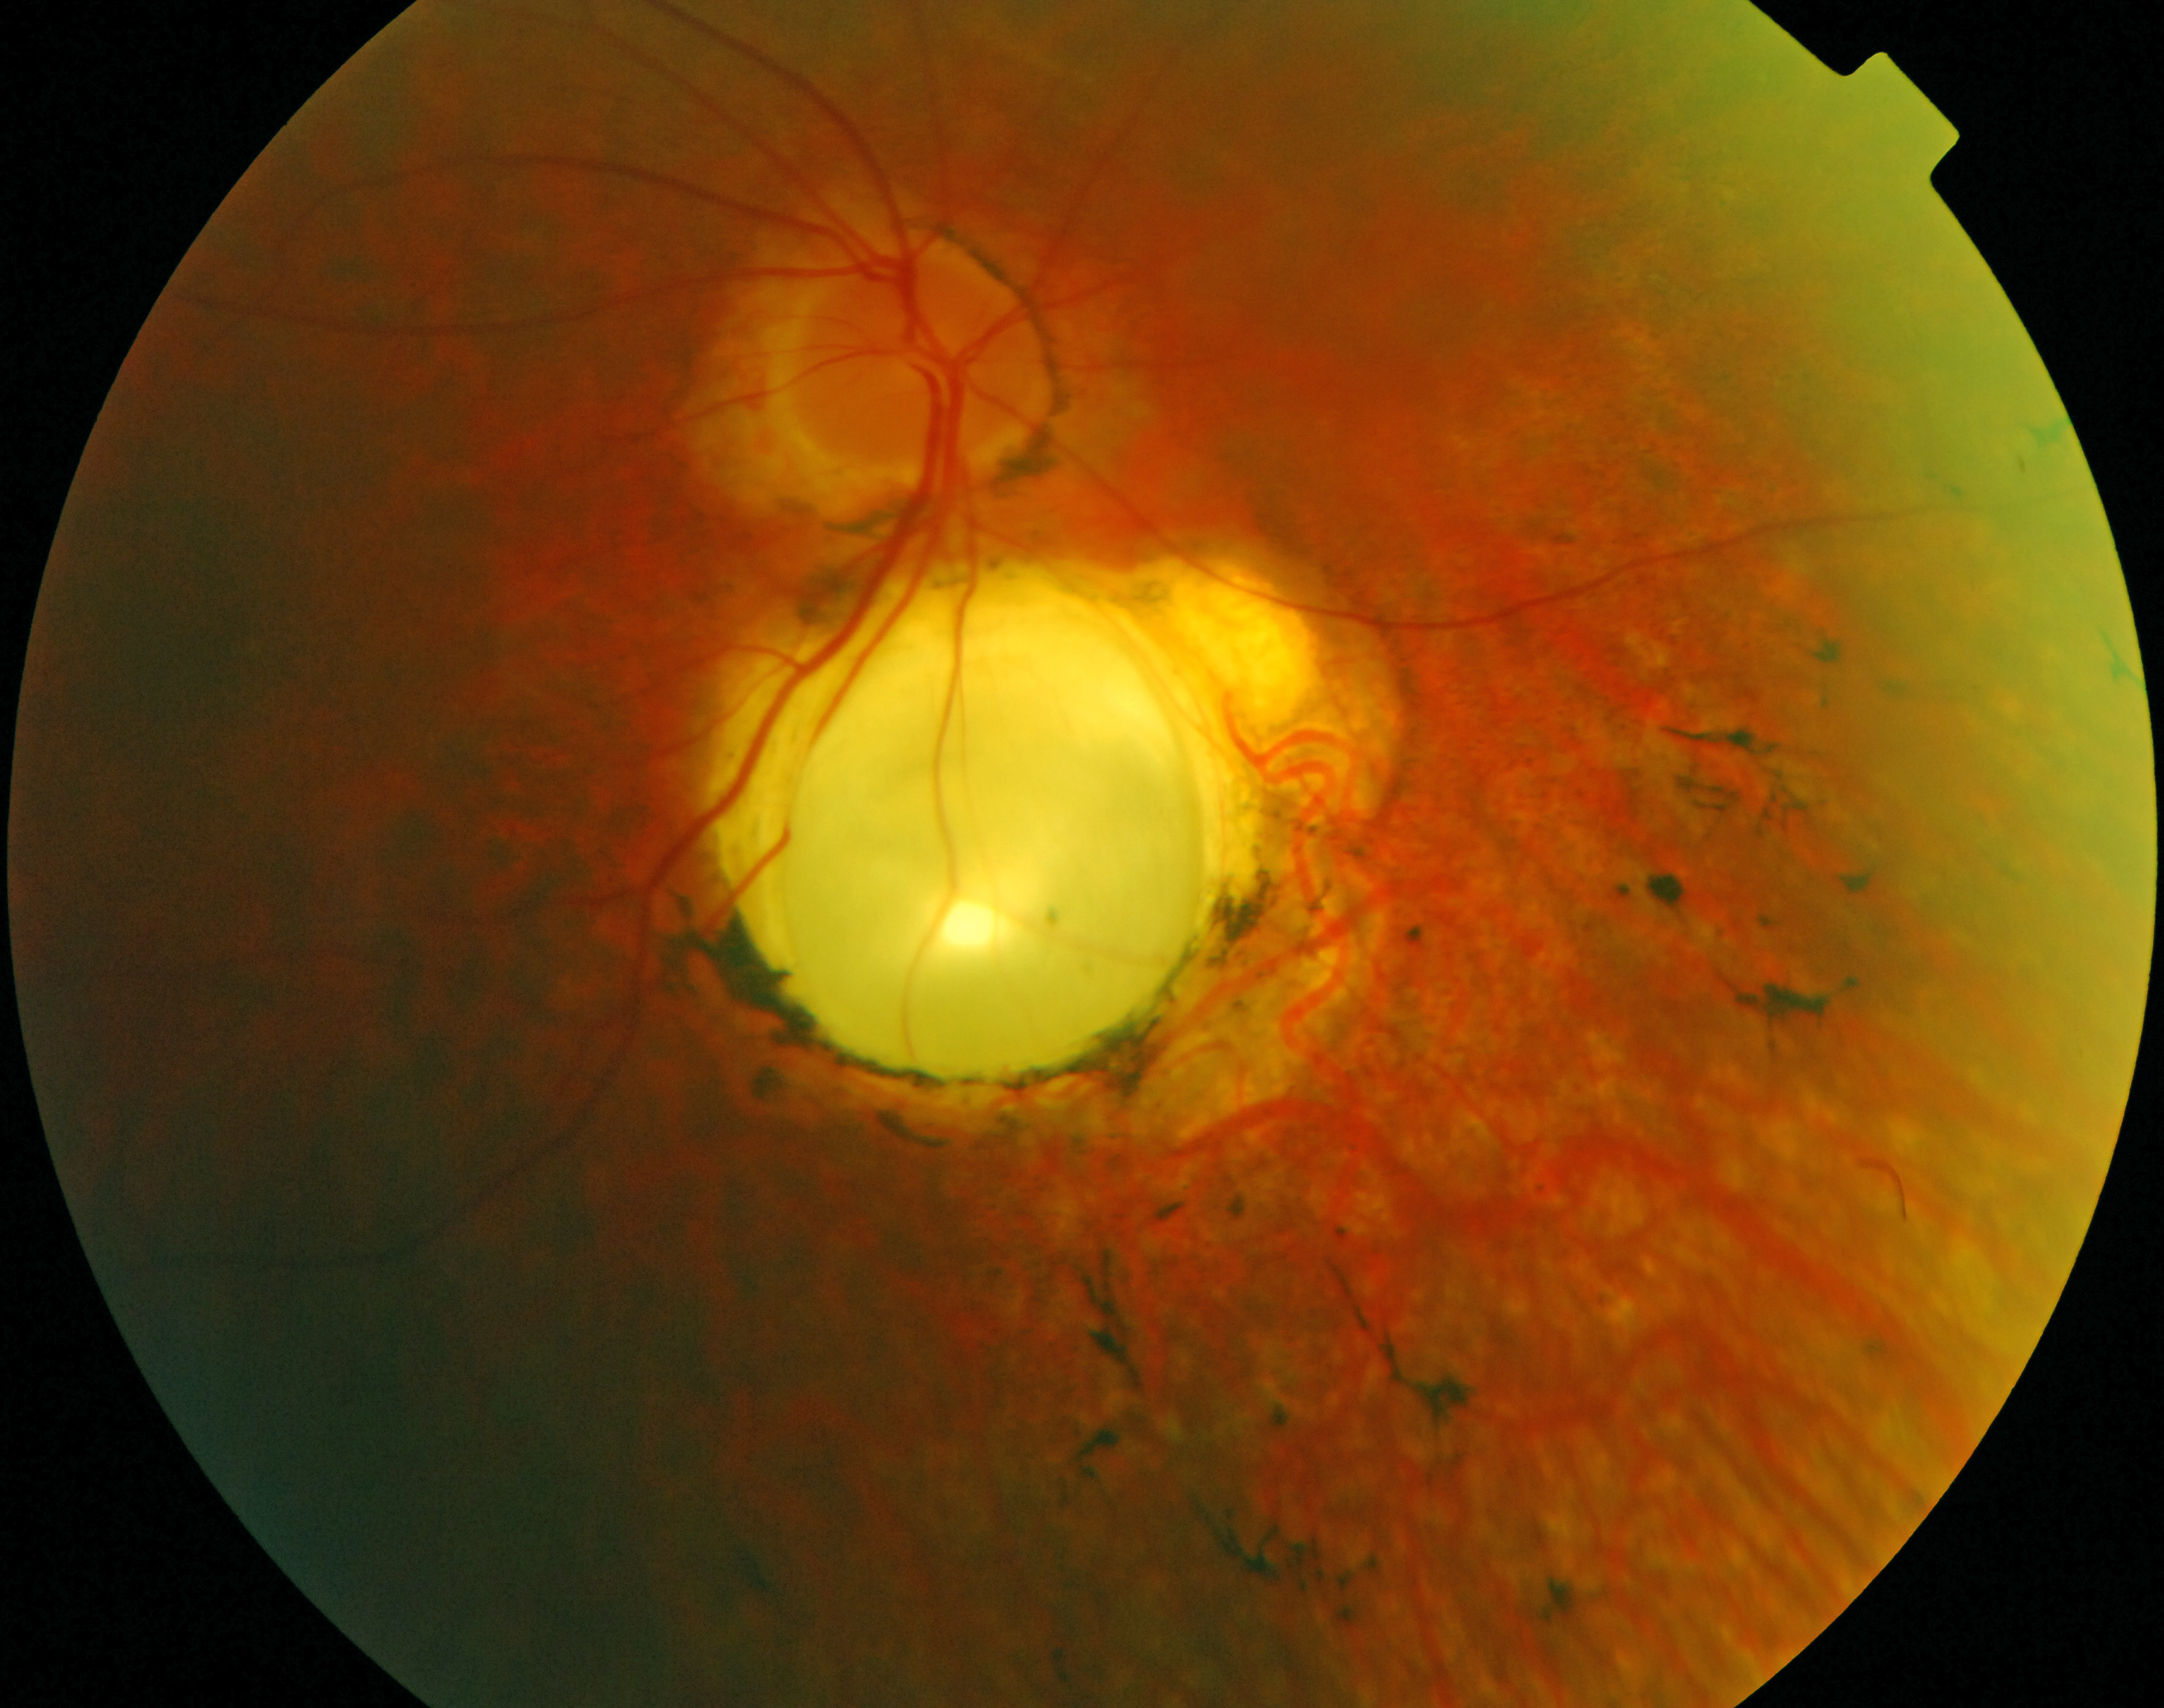

Figure 4. Fundus photograph of the

right eye of Patient 15 at age 38. Note the mild pallor of the

optic disc, the attenuation of the vessels, the chorioretinal

coloboma, the retinal pigment epithelium atrophy (RPE) atrophy,

and the bone spicule-like pigmentations.